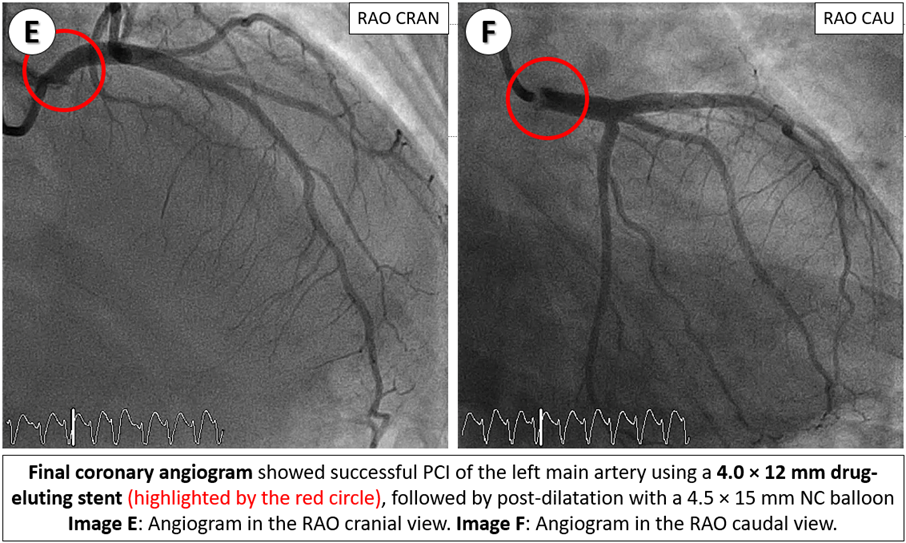

Emergency coronary angiography revealed a critical ostial left main stenosis with TIMI 2 flow and a normal right coronary artery. Following engagement with 6-Fr JL 4.0 side-hole catheter, sequential pre-dilatation was performed using 3.5x15 mm and 4.5x15 mm non-compliance (NC) balloons. A 4.0x12 mm drug-eluting stent was deployed in the left main artery, followed by post-dilatation with a 4.5x15 mm NC balloon. Subsequently, an intra-aortic balloon pump was inserted for hemodynamic support.